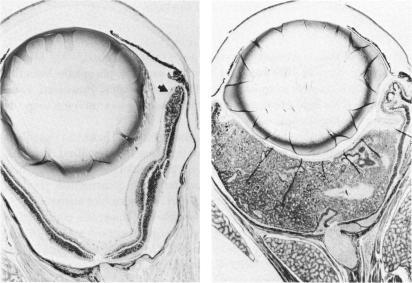

Transgenic models of retinoblastoma: what they tell us about its cause and treatment.

Trans Am Ophthalmol Soc. 1994;92:385-400; discussion 400-1.

PMID:7886874

原文链接:https://pmc.ncbi.nlm.nih.gov/articles/PMC1298518/